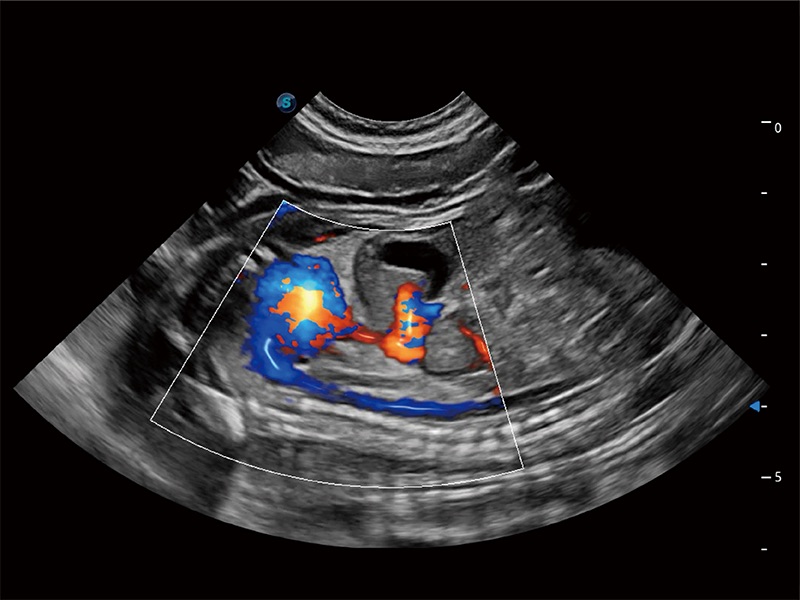

ProPet 80 配备了丰富的心脏探头群、先进的成像技术和专业的心脏测量工具,可帮助动物医生为不同体型和生理结构的动物提供心脏和心肌功能的全面评估。